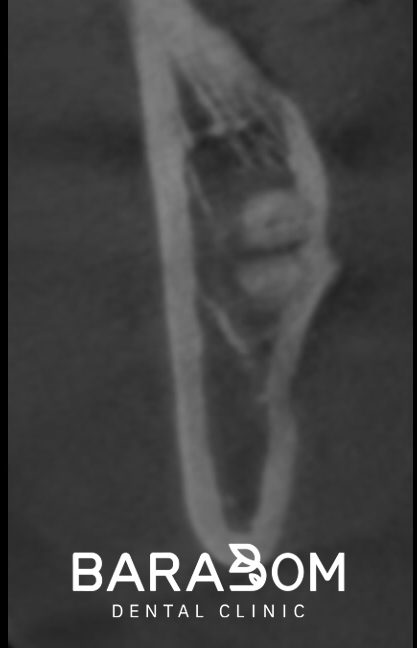

치아를 분할하여 제거한 후에는

치근이 남아있지 않은지

방사선 사진(PA)으로 확인합니다.

잔존 치근이 있으면

염증의 원인이 될 수 있기 때문이죠.